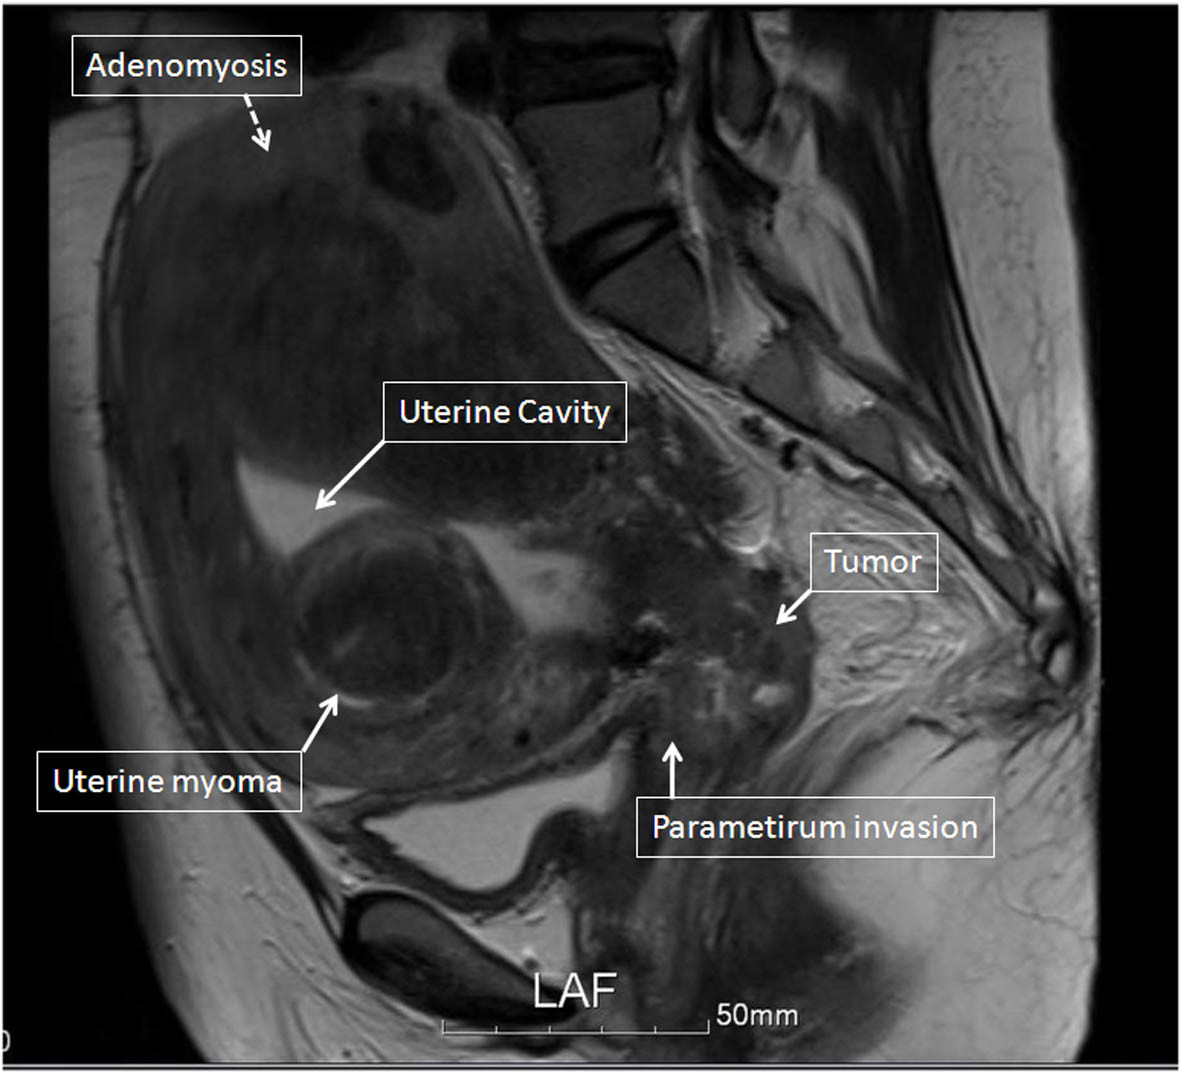

Figure 2

MR image of the pelvis before treatment shows direct invasion of the cervical tumor into the right parametrium, bilateral hydronephrosis, and multiple uterine myomas. The solid arrows indicate the parametrium invasion, the uterine myomas, the tumor, and the uterine cavity. The dotted arrow indicates adenomyosis.